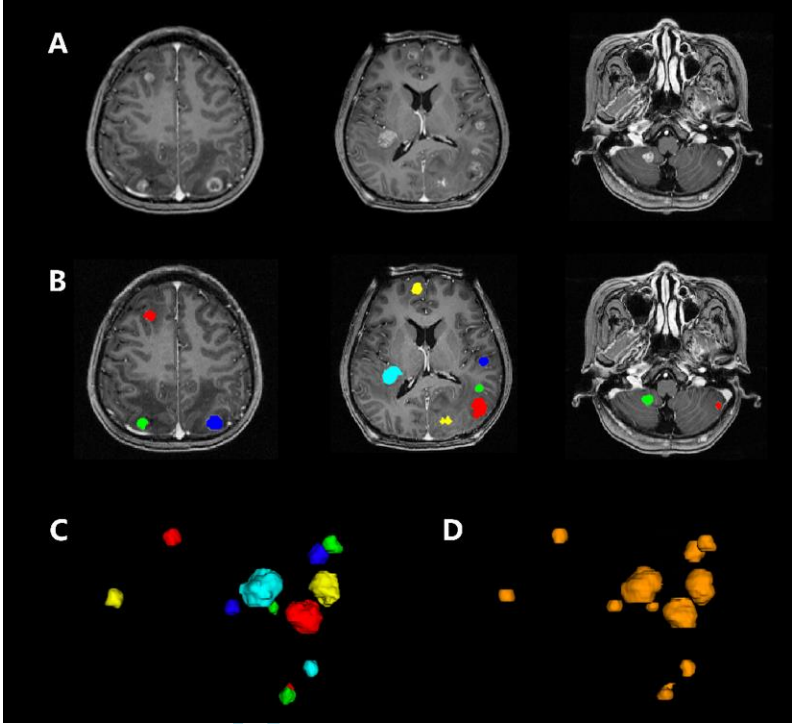

磁共振 T1加权三维磁化强度预备梯度回波序列(3D-T1-MPRAGE)是MRI中检测脑转移瘤(BM)的首选方法。作者对BM开发了一种利用3D-T1-MPRAGE图像基于深度学习的自动检测和分割算法(称为BMDS网络),并对其性能进行了评估。该BMDS网络是级联的3D全卷积网络(FCN),用于自动检测和分割BM。文中总共纳入了3家医院1652例患者的3D-T1-MPRAGE图像(分别为n=1201、231和220),由神经放射科医生和肿瘤放射科医生共同在3D-T1-MPRAGE图像中进行手动分割,评估分割的敏感性,特异性和骰子比。特异性和敏感性用于评价所分割的相关部分,骰子比率用于定量测量自动和手动分割结果之间的重叠。用配对样本t检验和方差分析进行统计分析。结果发现,BMDS网络可以检测到图像上所有的BM,检测结果达到100%的准确度。通过对1201例患者的数据集进行4倍交叉验证,自动分割与手动分割密切相关:敏感性为0.96±0.03(范围0.84-0.99),特异性为0.99±0.0002(范围0.99-1.00),肿瘤总体积的骰子比为0.85±0.08(范围0.62-0.95)。 BMDS网络准确检测和分割BM的鲁棒性在其他2个数据集上也得以验证。因此,该BMDS网能自动准确地检测和分割BM,有助于立体放射治疗专家对诊断、治疗计划和随访的管理。

利用BMDS网络分割多个脑转移瘤。图为一67岁男性肺癌脑转移患者。3D T1-MPRAGE增强图像显示脑内多发转移灶(A)。(B)使用不同颜色的标签手工分割,(C)肿瘤的手动分割空间视图,BMDS网络自动分割(D)与手动分割高度一致。